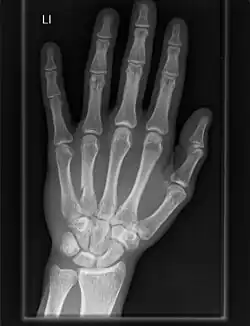

Importancia clínica

La artrosis de las articulaciones carpometacarpianas es un tipo de enfermedad articular que resulta de la descomposición del cartílago articular y del hueso subyacente.[9] Cuando afecta al pulgar se denomina artrosis trapeciometacarpiana.

El saliente carpometacarpiano es la presencia de una pequeña protuberancia inmóvil sobre la articulación.[10]